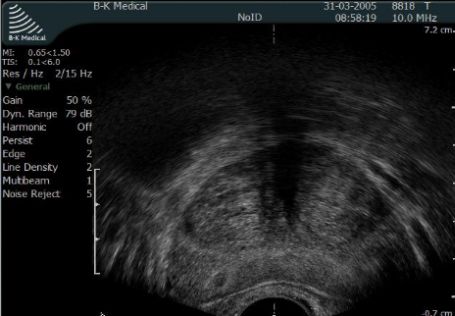

Urolodzy bardzo rzadko opisują echostrukturę gruczołu krokowego ocenianą w trakcie USG brzucha. Aby precyzyjnie ocenić echostrukturę gruczołu krokowego konieczne jest wykonanie USG transrektalnego - specjalna głowica do USG przezodbytniczego. Zwapnienia - czyli hiperechogenne odbicia mogą pochodzić z tkanki zrębowej gruczołu krokowego lub z kamieni sterczowych. Obraz stercza w USG wykonanym przez powłoki brzucha nie ma związku ze stanem ogólnym gruczołu krokowego.

Fot. Gruczoł krokowy w USG transrektalnym - przekrój poprzeczny.